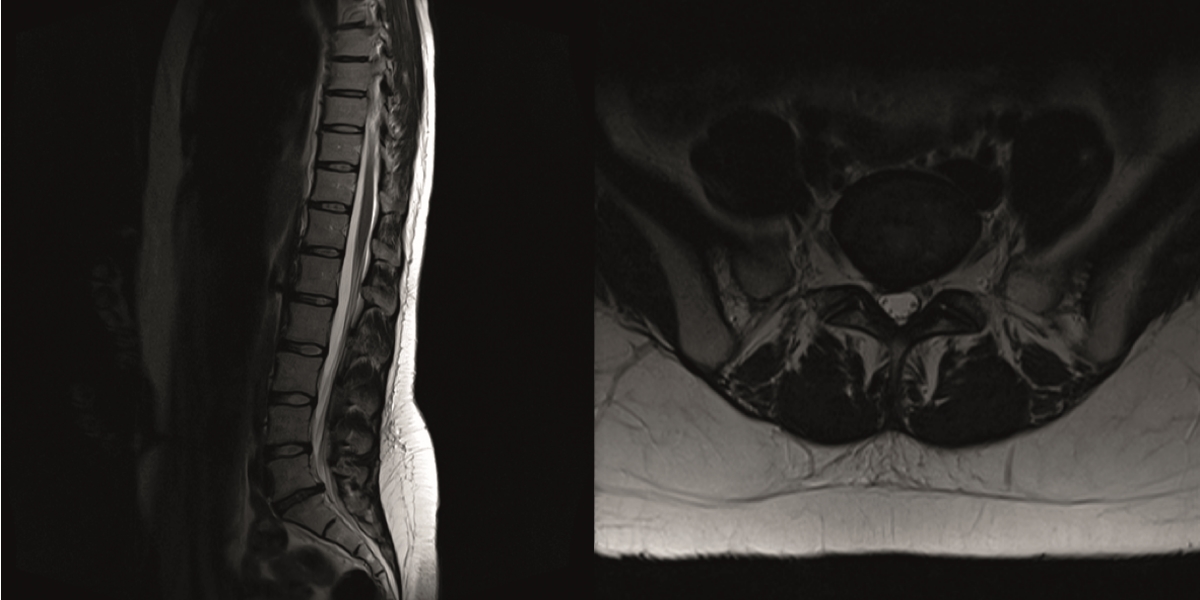

The sagittal and axial T2-weighted MRI showed grade III disc degeneration with diffuse right-sided disc bulging (Fig 12).